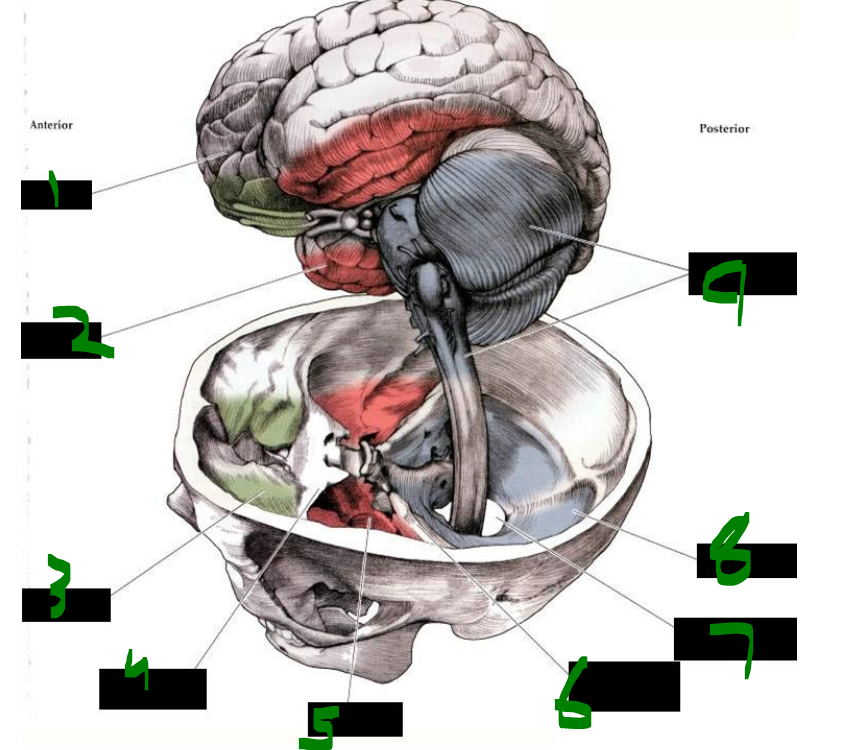

1

card image

What is 1?

mesencephalon (midbrain)

2

What is 2?

metencephalon

3

What is 3?

medulla

4

What is 4?

inferior olive

5

What is 5?

pons

6

What is 6?

inferior colliculus

7